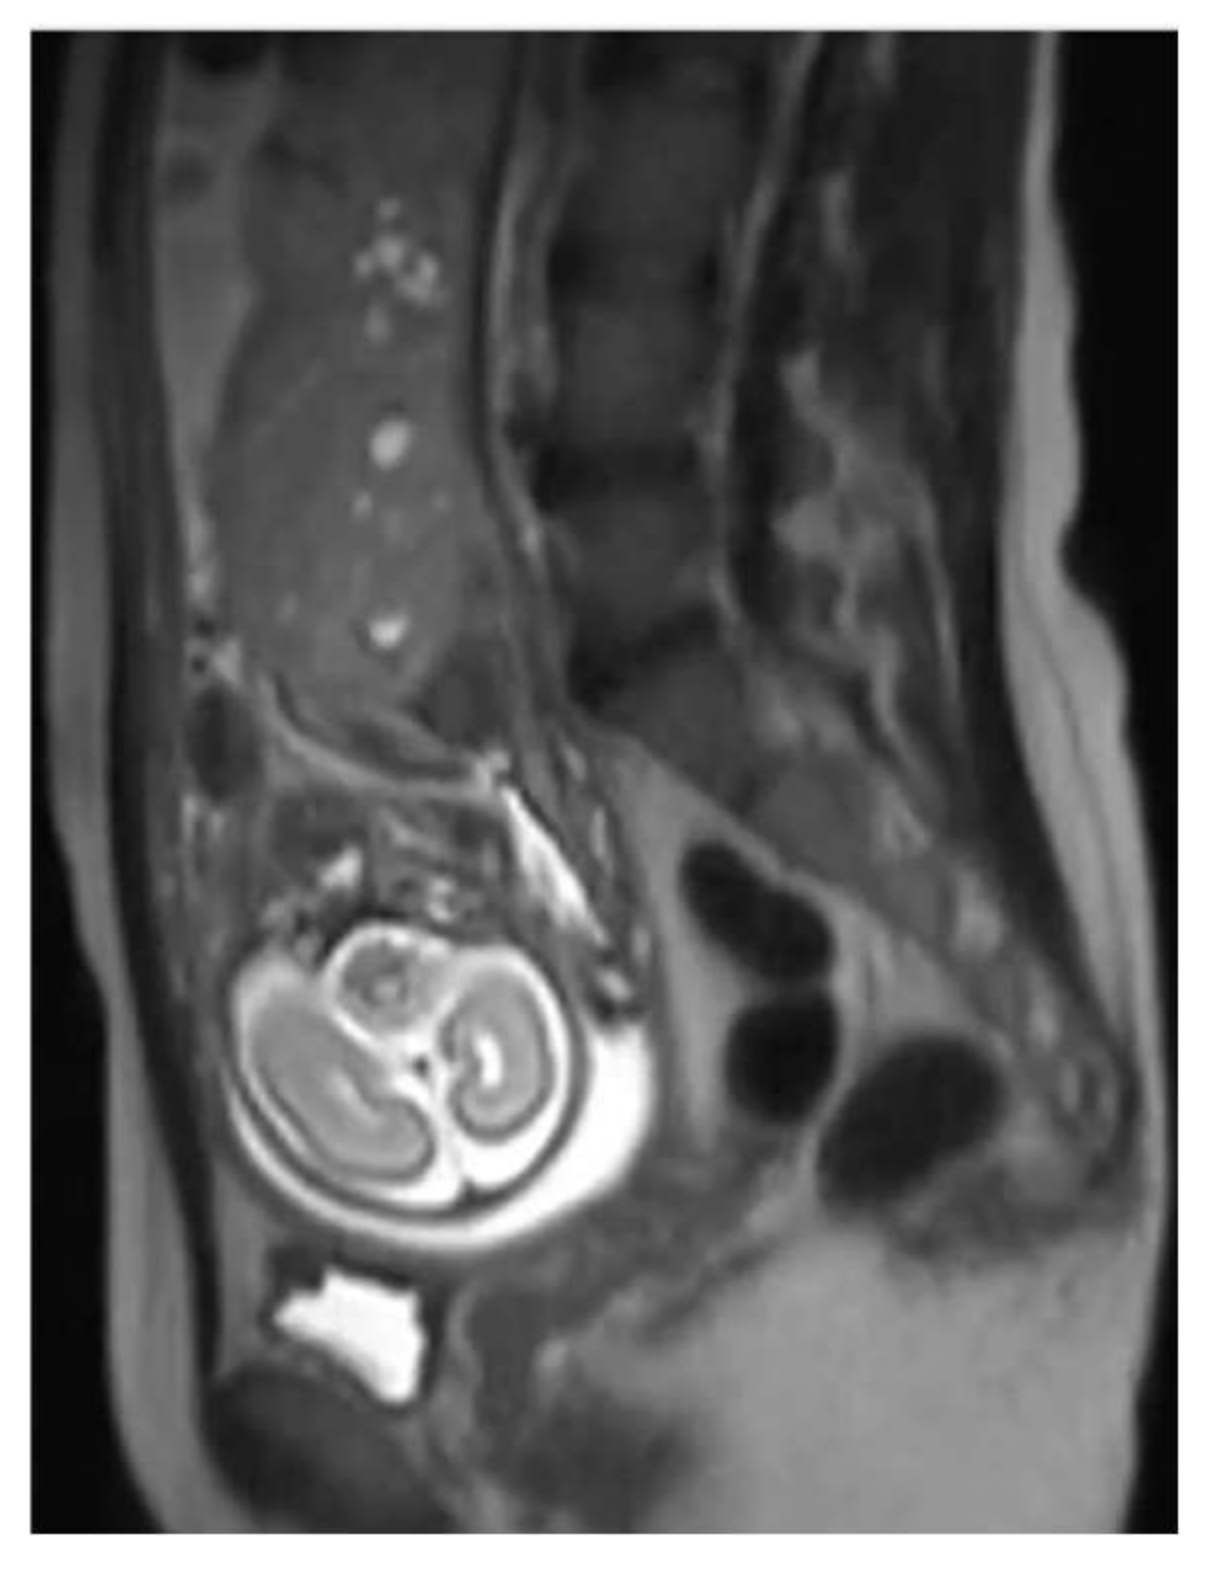

3. Case Report